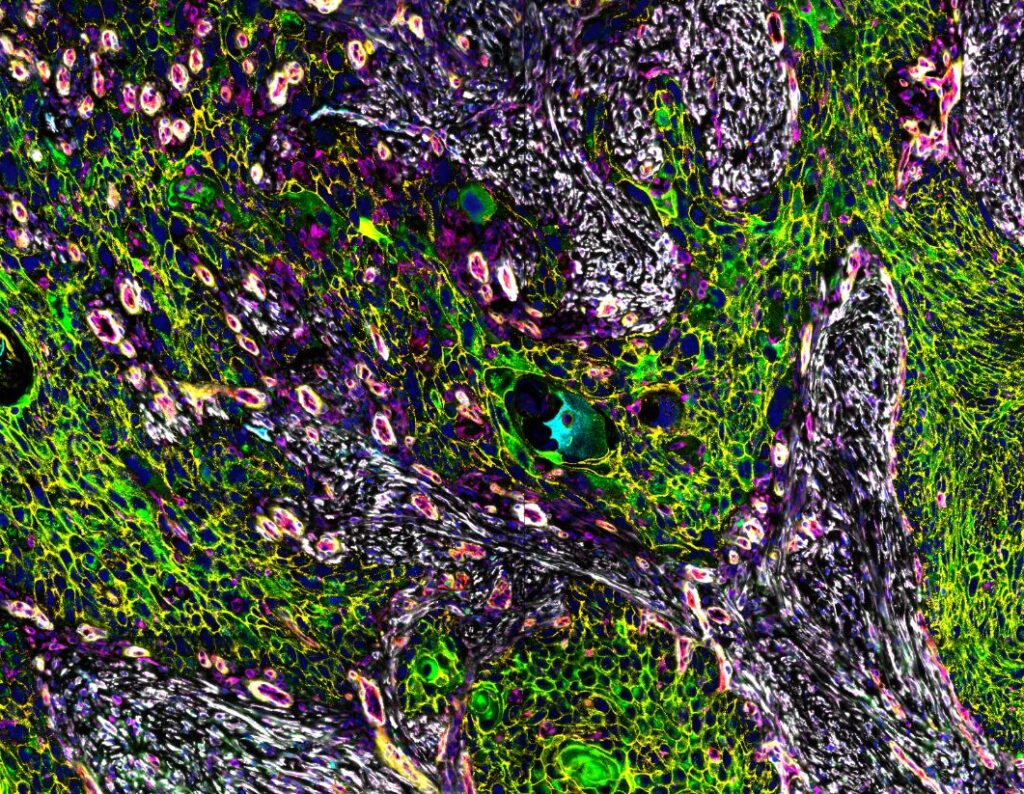

The CellScape Data Explorer gives you an interactive, in-browser view of real high-plex spatial proteomics datasets generated with VistaPlex™ Assay Kits and the simple, straightforward CellScape platform workflow. Each dataset showcases the CellScape platform’s ability to capture broad tissue architecture and unparalleled cellular detail within the same field of view, letting you zoom seamlessly from large-scale structure to single-cell features while maintaining best-in-class resolution and high dynamic range.

Across all datasets, you can toggle individual markers, survey vast or precise regions of tissue, and see real-world data from each of our VistaPlex Multiplex Assay Kits to evaluate staining specificity and marker localization. Integrated phenotype and segmentation overlays help you quickly visualize cellular organization, tissue compartments, and spatial relationships, providing a clear sense of panel performance and biological resolution without needing to download any files.